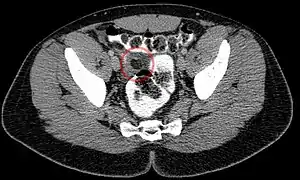

Abdominal CT scan, epiploic appendagitis (circle)

Ultrasound and CT scans are the normal means of positive diagnosis of epiploic appendagitis. Ultrasound scans show "an oval, non-compressible hyperechoic mass with a subtle hypoechoic rim directly under the site of maximum tenderness".[5] Normally, epiploic appendages cannot be seen on CT scan.[5] After cross-sectional imaging and the increased use of abdominal CT for evaluating lower abdominal pain, EA is increasingly diagnosed. Pathognomonic CT scan data represent EA as 2–4 cm, oval shaped, fat density lesions, surrounded by inflammation. Contrasting with diverticulitis findings, the colonic wall is mostly unchanged.